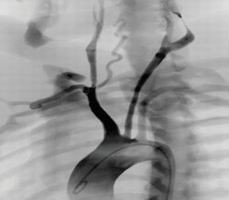

頸動脈介入手術(shù)模塊

可練習(xí)頸動脈支架手術(shù)的完整過程:造影診斷、導(dǎo)絲通過、導(dǎo)引導(dǎo)管的放置、保護(hù)傘的放置、預(yù)擴張、自擴張支架放置、后擴張、以及再造影等。